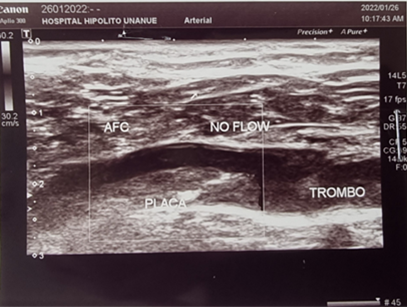

La evaluación laboratorial inicial, solo evidenció un dimero D levemente elevado, no se identificó infección activa ni coagulopatía alguna. El estudio bioquímico no reveló infección viral de hepatitis, lesión renal aguda o algún desequilibrio electrolítico. Mientras que el perfil antifosfolipídico fue normal. En la ecografía doppler se evidenció una oclusión significativa a nivel de arteria femoral común izquierda (Figura 2) y con la angiotomografía contrastada (angio-TAC) (Figura 3), se confirmó la oclusión completa de la arteria ilíaca izquierda con colaterales que proporcionan flujo sanguíneo a ambas arterias iliacas externas y la designación del síndrome como tal, iniciando con antiagregante plaquetario, estatinas y tratamiento por cirugía vascular, debido a la amenaza inmediata de pérdida de la extremidad afectada.

Figura 2 Ecografía doppler de los miembros inferior izquierda, se evidencia una oclusión significativa a nivel de arteria femoral común izquierda.

El síndrome de Leriche se diagnostica a través de estudios vasculares no invasivos, como: la ecografía doppler y la angio-TAC; o estudios invasivos como: la angiografía convencional, siendo éste último, considerado como el estándar de referencia para el diagnóstico8, dichas imágenes nos permiten también definir el sitio de obstrucción, el grado, la presencia de circulación colateral y la permeabilidad distal9,13. En nuestro caso, el diagnóstico fue confirmado con la angio-TAC e inicio manejo multidisciplinario con cirugía vascular, traumatología y medicina interna.